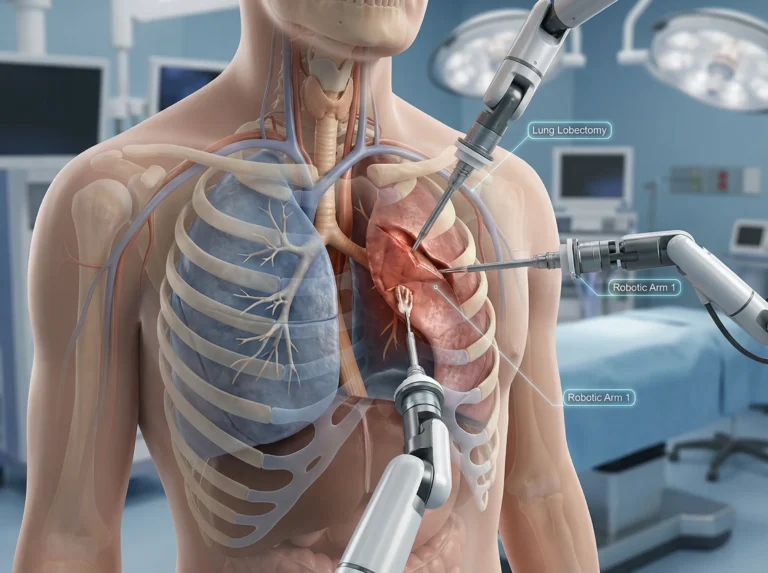

If you or someone you love has been told that surgery may be needed for a chest condition whether it’s related to…